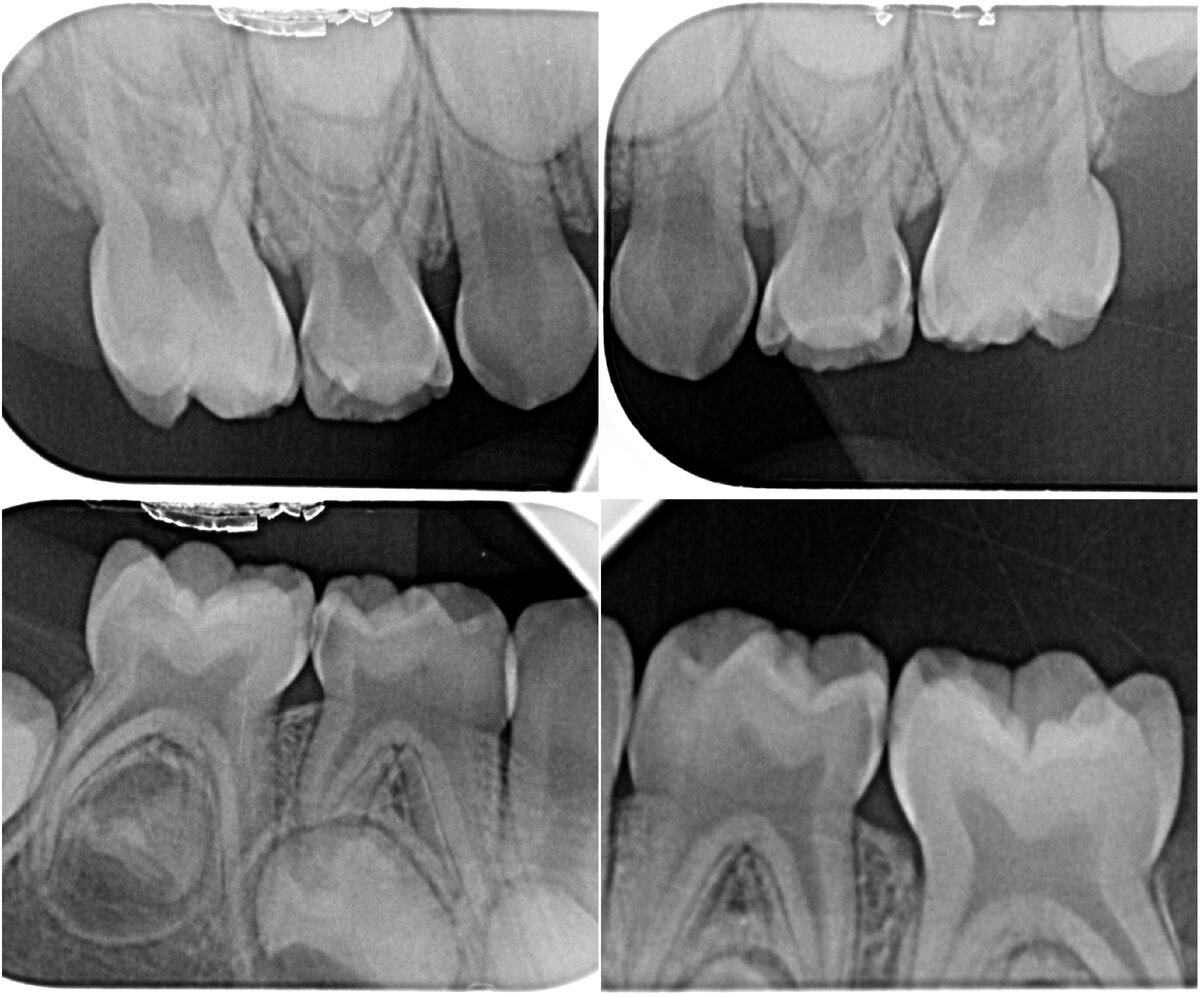

Вот так выглядит комплекс прицельных снимков жевательной группы зубов (4 штуки). Видны все корни, кость между корнями и вокруг них, все поверхности зуба, нет наложения проекции одного зуба на другой.

7. Теперь самый главный этап. Рентгенография! Обязательно нужны снимки! Для диагностики, в том числе кариеса "между зубами" нужны маленькие (прицельные) внутрироторые снимки. Не панорамные, а прицельные! Только с такими снимками мы можем оценить все поверхности зуба, состояние корней, кости вокруг зуба и связки, которая его держит.